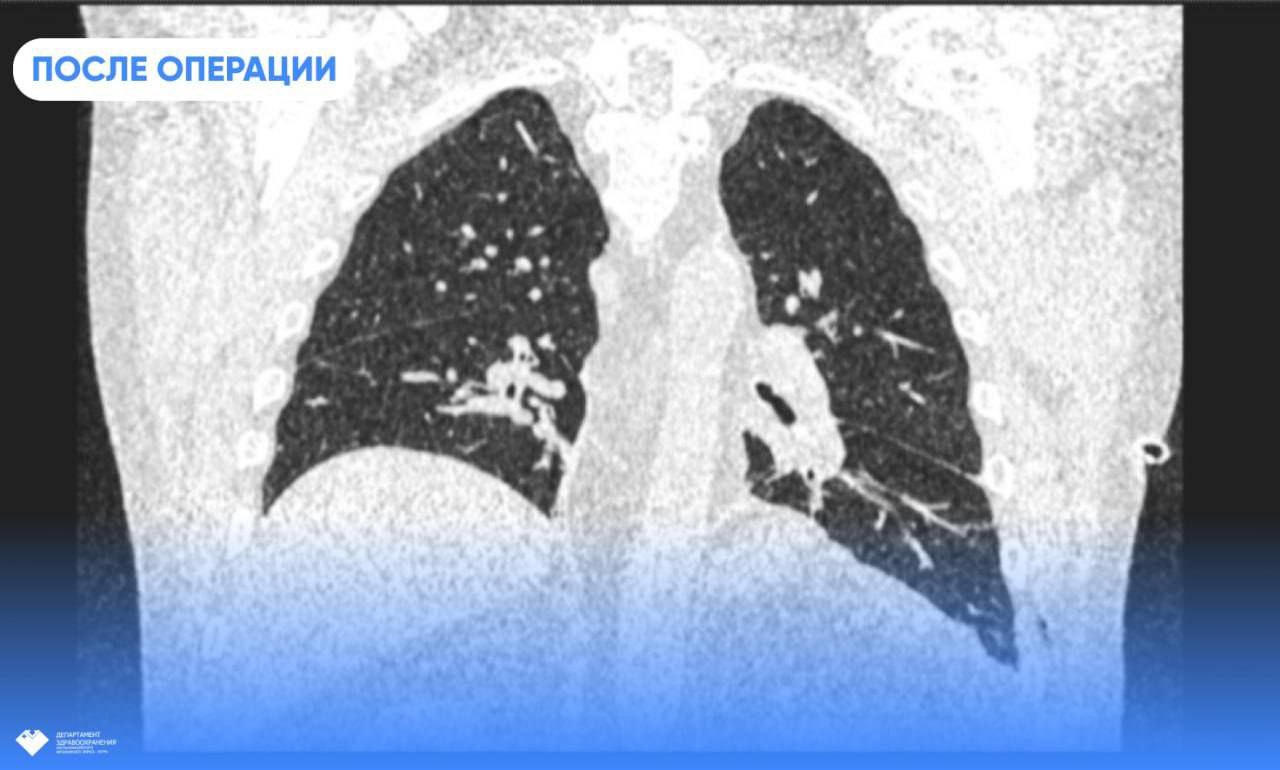

Лечение – только хирургическое. Пластика диафрагмы – это особая техника наложения шва. Операция ювелирная, поскольку толщина диафрагмы не превышает 5 миллиметров, и есть риски повредить окружающие структуры. С задачей успешно справились заведующий хирургическим отделением травмбольницы, главный торакальный хирург Югры Дмитрий Горлов и врач-хирург Евгений Николаев. Они предпочли малоинвазивную торакоскопическию методику, избежав травматического полостного доступа и дополнительной нагрузки на организм пациента.

Сразу после операции Юрий Александрович почувствовал улучшение самочувствия. Одышка больше не беспокоит, и сегодня он вновь может дышать полной грудью. Его качество жизни не пострадает. Единственное ограничение касается физических нагрузок, но и это условие необходимо соблюдать только в течение первого месяца.